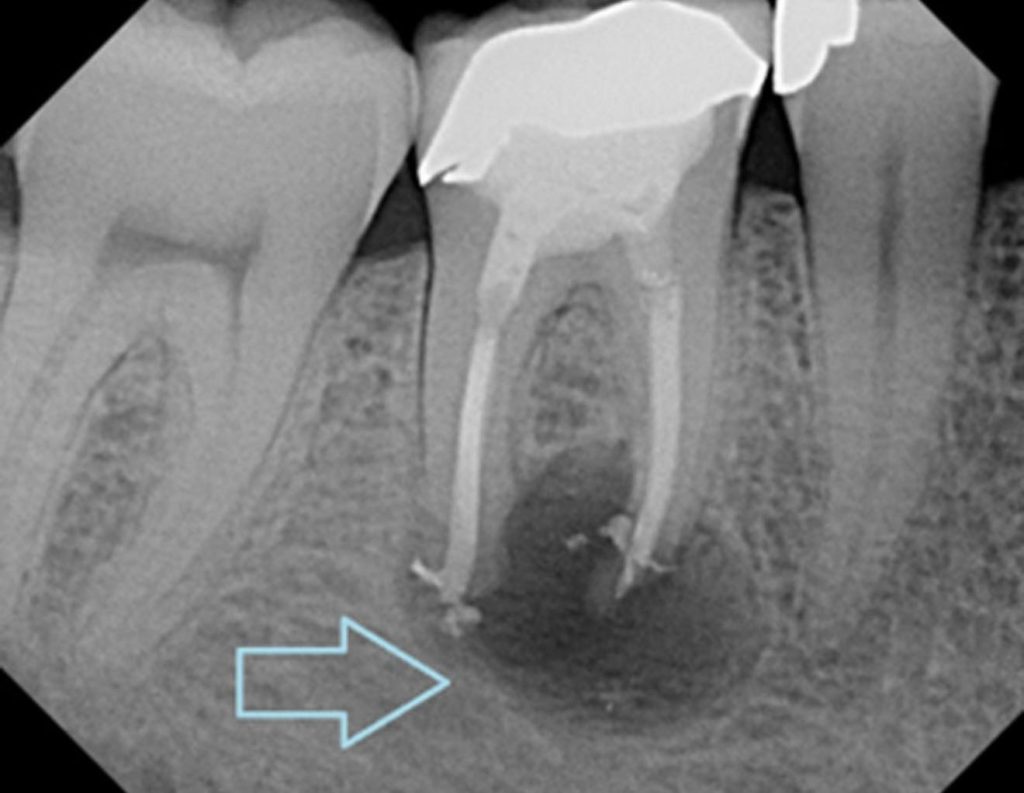

3. რატომ არ შეიძლება ანთებითი კბილის იგნორირება?

კბილის პულპის (ნერვის) ანთება (პულპიტი ან პერიაპიკალური ინფექცია) არ არის მხოლოდ ლოკალური პრობლემა.

ინფექცია შეიძლება გავრცელდეს ძვალზე, მეზობელ ქსოვილებზე და ზოგ შემთხვევაში გამოიწვიოს სისტემური გართულებები.

თანამედროვე მედიცინა აღიარებს, რომ ქრონიკული კბილის ინფექციები ზრდის ორგანიზმში საერთო ანთებით ფონს.

ტკივილის არ ქონა არ ნიშნავს პრობლემის აღმოფხვრას – ძვლის დესტრუქციული უბანი საჭიროებს დროულ და სწორ მკურნალობას